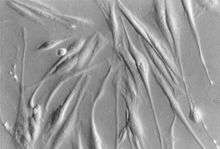

Cultured pancreatic stellate cells in varel contrast microscopy

Pancreatic stellate cells (PaSCs or PSCs) are myofibroblast-like cells that can switch between the quiescent and activated phenotypes, like hepatic stellate cells.[2] PaSCs reside in exocrine areas of the pancreas. When activated, PaSCs migrate to the injured location, and participate in tissue repair activities, secreting ECM components. PaSCs may play a role in the pathogenesis of pancreatitis and pancreatic cancer.[1]